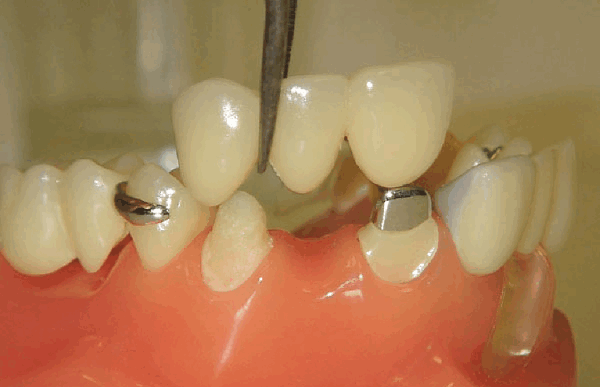

Когда обточат зубы, что-нибудь наденут на культю? Или так и ходить с острыми клыками

После препарирования зубов на них надеваются защитные временные коронки до установки постоянного протеза

Установка временных конструкций. Иногда при подготовке к несъемному протезированию может потребоваться временный протез. Врач устанавливает его, чтобы снизить дискомфорт, пока вы ходите без зубов.

Сточенную эмаль временный (адаптационный) протез защищает от бактериального воздействия, перепадов температур, попадания пищи до установки постоянного.